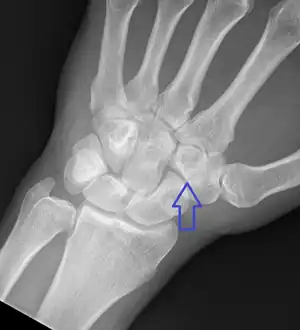

| Nondisplaced fracture through the lateral trapezoid bone | |

Trapezoid fracture is a break of the trapezoid bone of the wrist. Symptoms generally include wrist pain inline with the index finger.[1] They are often associated with other wrist fractures or dislocations.[1] Complications may include arthritis.[1]

Causes may include trauma, a direct blow, or excessive forced bending of the wrist.[1] Types are dorsal rim and body.[1] Diagnosis is typical by X-rays or CT scan.[1]

Treatment of fractures that are well aligned is by orthopedic casting for 4 to 6 weeks.[1] Otherwise surgery is generally indicated.[1] Outcomes appear to be generally good.[1] Trapezoid fractures represent less than 1% of wrist bone fractures.[1] It is the rarest broken wrist bone along with the pisiform.[2]